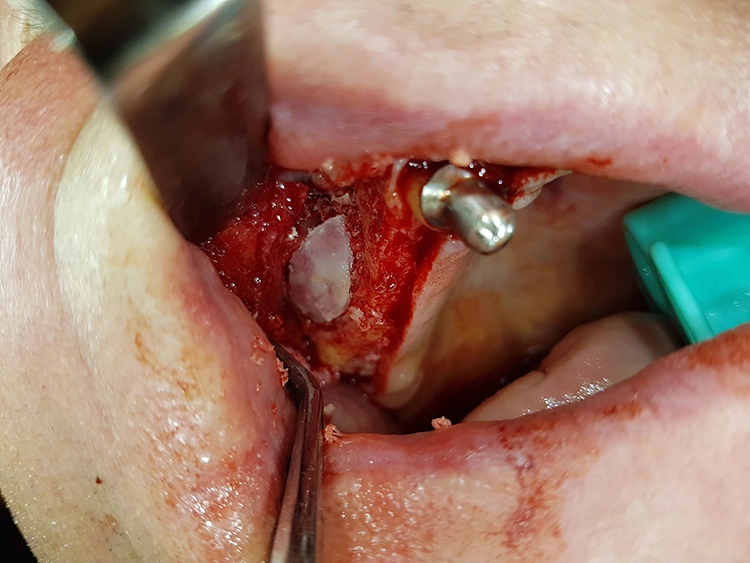

Zeitgleich mit der Freilegung wurde Zahn 13 extrahiert. Nach sorgfältiger Exkochleation wurde die unversehrte Alveole im Sinne einer Socket Preservation mit bovinem Knochenersatzmaterial (MinerOss X) verfüllt und mit einer porcinen Kollagenmembran (MemLok Pliable) abgedeckt. Damit lässt sich ein postoperativer Gewebeabbau und eine Einschränkung der Weichgewebeästhetik unter einem Brückenglied weitgehend vermeiden: Die Socket Preservation mit bovinem Knochenmineral und porciner Kollagenmembran schränkt die horizontale und vertikale Knochenresorption im Vergleich zur alleinigen Extraktion erheblich ein (Abb. 19 und 20) [1,6,9].